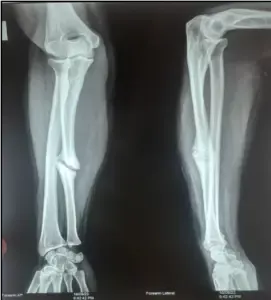

The patient was on Puttur bandage, but she removed the bandage within 4 weeks and by her complaints and the results of her prior X-rays diagnosed as nonunion of the right ulnar. She was taking medication, and when she approached an allopathic hospital, they recommended surgical reduction, but the patient was unwilling. For better care, she came to our hospital. Physical examination revealed difficulty in downward and upward movement of forearm and the power was 1/5. Pain, edema, local tenderness and stiffness over forearm and fingers were observed at the initiation of the Ayurvedic treatment.

In Ayurveda we advised her for Sastra Karma (Surgical intervention), but the patient was unwilling. So, we treated her with Samana Chikitsa (Internal medications) and Bahya Chikitsa (External therapy). The complaints presented by the patient together with the interpretation of anteroposterior and lateral views of the X-ray right forearm, were diagnosed as ulnar shaft fracture

Before intervention